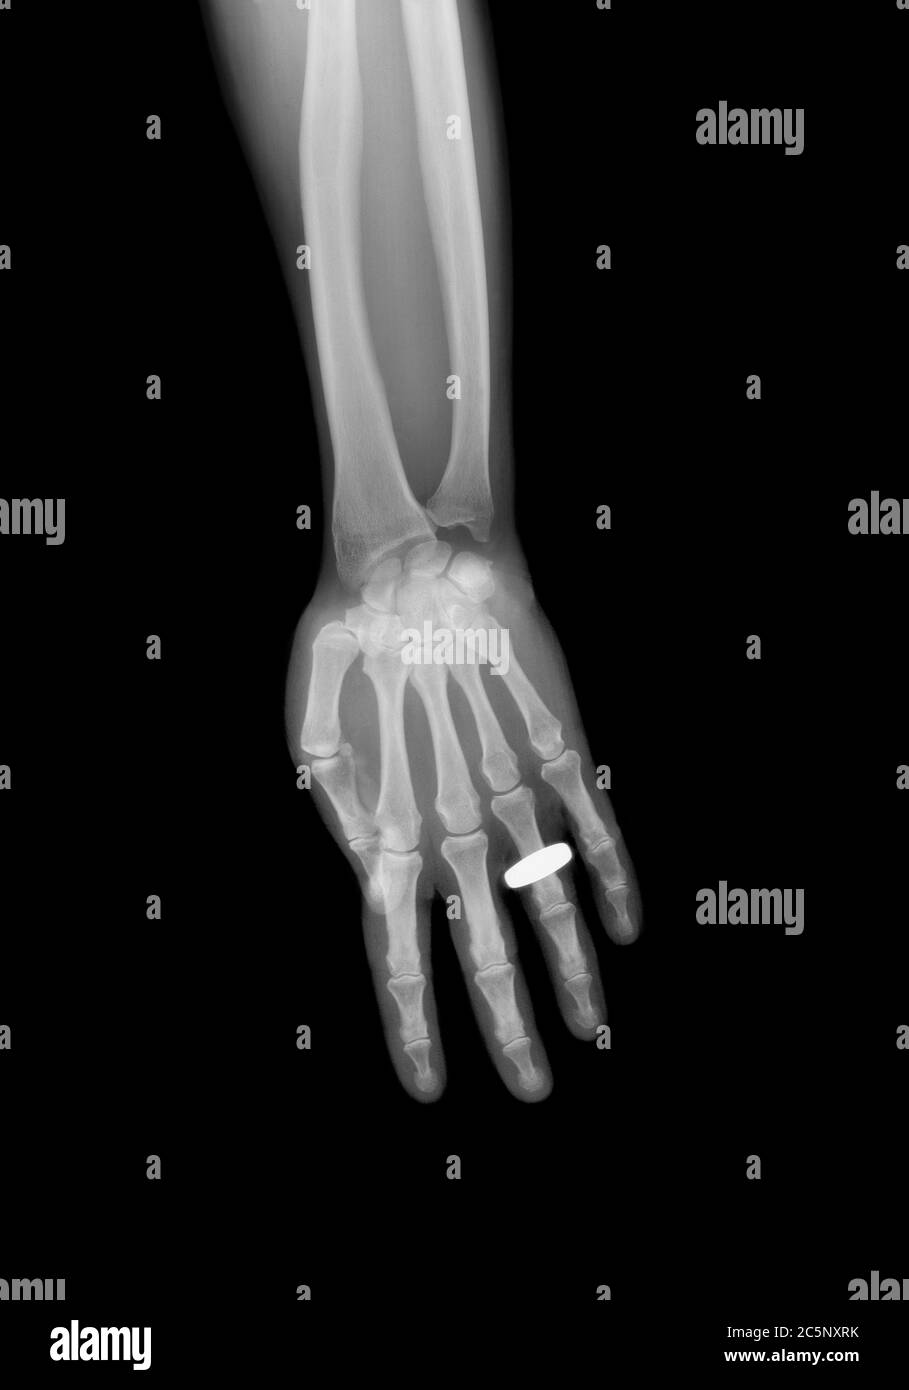

Hand bones Xray with a ring Stock Photo Alamy Ring Finger X Ray This projection is useful for diagnosing fractures and localizing foreign bodies in pediatric patients. Notice how the fracture tends to slip or shorten (arrow). The series examines in detail the distal, middle and proximal phalanx as well as. The hand comprises the metacarpal and phalangeal bones. The finger series is comprised, conventionally of a posteroanterior, oblique and a lateral view. Ring Finger X Ray.

The bones of a hand with a ring on one finger, viewed through xray Ring Finger X Ray The hand comprises the metacarpal and phalangeal bones. The series examines in detail the distal, middle and proximal phalanx as well as. Notice how the fracture tends to slip or shorten (arrow). The finger series is comprised, conventionally of a posteroanterior, oblique and a lateral view. This projection is useful for diagnosing fractures and localizing foreign bodies in pediatric patients. Ring Finger X Ray.